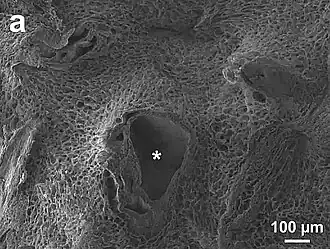

Espacio periportal

Se llama espacio periportal, de Mall o de Kiernan, a la zona estrecha en forma de cuña que rodea la "tríada porta". Es la continuación de la vaina de Glisson, la parte de la cápsula que rodea el sistema porta y se extiende dentro del espesor del hígado.[6]

El espacio peri-portal (PPS) es tejido conjuntivo laxo, constituido por células y fibras. Las células son fibroblastos y las fibras principales de la matriz extracelular (ECM en inglés), son tipos de colágeno, colágeno tipo I, colágeno tipo III, colágeno tipo IV, además de fibronectina, elastina, laminina y glucosaminoglucano.[7][8][9]

El tejido periportal sirve de soporte y armazón a: la tríada portal, los nervios y los linfáticos que siguen este camino de tejido conectivo a través del hígado.[10][3][11]